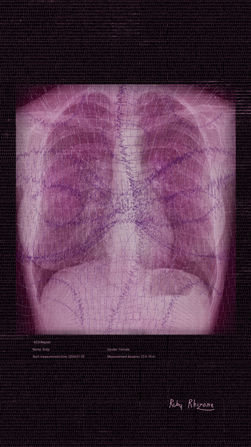

GENESIS project is a blockchain native project based on medical and body data by Ruby Rhizome. As an artist exploring blockchain technology on a larger philosophical and technological scale, Ruby Rhizome sees its enormous potential, viewing it as an antidote, and perhaps even a cure, for a post-capitalistic society. She believes it opens a door to new socio-cultural changes that society has been seeking. In her creative and personal philosophy, she is drawn to Deleuzian approaches of interconnectedness and post humanistic ideas where one entity connects to another. Consequently, in her art, she seeks that interconnected thread, challenging the dualistic manner of viewing the world. In her GENESIS project, she focuses on human-digital/intimate-public dualisms, challenging them and pushing her own boundaries. This work is not only philosophical but also possesses a simplicity—it is a celebration of life, almost life itself. Since undergoing a serious surgery a few years ago, Ruby Rhizome experienced a profound realization of being alive for the first time—and, naturally, has been very grateful for it. She vividly remembers how happy that seemingly simple fact made her. Since then, Ruby Rhizome has always found medical data strangely beautiful—certificates of our existence, proven by data and measurements. After accumulating a lot of her medical data in her artistic studio and observing them for their peculiar beauty and the satisfaction they gave her, contemplating her existence, she decided to turn it into artwork. As she was wearing actively and consistently an AI-powered ECG holter reader for months and recording all of her heartbeats, she also underwent an X-ray of her upper body and lungs, where the lungs, spine, heart, and chest are visible. Then, she extracted measurements of her 24-hour heartbeats foe many days and hand -manipulated them into a drawing lines using various digital softwares. For her, the heartbeats themselves became an artistic medium. The scan of Ruby Rhizome's upper body serves as a canvas—an embodiment of the concept that our bodies are mere vessels for life. Each artwork is colored differently as each work portrays different emotion that artist experienced that day. Each artwork contains details of the ECG measurement with a highlighted date of recording, and Ruby Rhizome's signature. Thus, each artwork is inherently unique, reflecting the individuality of the day those heartbeats portray. By sharing this work on-chain, Ruby Rhizome aims to infuse it with a distinctly human essence. While digital art can often feel detached and impersonal, this project seeks to transcend that perception. It endeavors to bridge the gap between the cold, digital realm and the intimate human experience, uniting them through personal data. In Rhizome's work, the shapes are deeply rooted in sacred geometry and patterns, serving as a exploration in her research in the field of cymatics. By exploring the conclusions of Hans Jenny, by which everything is essentially a physical manifestation of vibration and frequency, with all physical shapes 'programmed' by these frequencies and sound vibrations. Inspired by this research which showcased structures reminiscent of mandalas and other recurring forms in nature, Rhizome realized that these shapes were manifestations of an invisible force field of vibrational energy. This observation affirmed that all forms are interconnected through the lines running through main points, known as 'nodal patterns.' Rhizome's work is heavily influenced, with many pieces in her collection incorporating shapes based on patterns detected by a cymascope during heartbeat readings. Additionally, other shapes present in the artist’s works, formed by her using heartbeats as a digital drawing medium, are derived from sound frequencies and simple geometry recurrently found in nature and the human body, such as the Fibonacci sequence, the golden ratio, and mandalas. The project's overarching goal is to dismantle the cultural barriers that separate the intimate from the public, the human from the digital. It seeks to illustrate the interconnectedness of all things and the shared nature of personal data—something both unique and universally relatable. In essence, this project represents an effort to humanize the blockchain, infusing it with the warmth and depth of human experience.